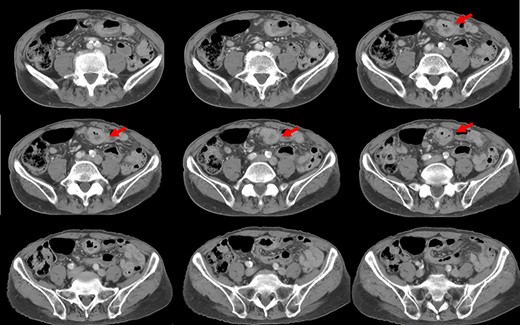

Preoperative computed tomography (CT) revealed a tumor in the sigmoid colon accompanied by some regional lymph node swelling (Fig. 1). It also showed that the IVC ascended vertically along the left side of the abdominal aorta. After connecting with the left renal veins, the left-sided IVC crossed the abdominal aorta anteriorly to join the normal prehepatic segment of the IVC (Figs 2 and 3). Coronal CT showed that the descending colon misplaced at the abdominal midline and the sigmoid colon in the right upper abdomen (Fig. 4). The preoperative diagnosis was thus sigmoid colon cancer with left-sided IVC and PDM.

CT shows that, after connecting with the left renal veins, the left-sided IVC (arrows) crosses the abdominal aorta anteriorly to join a normal prehepatic segment of the IVC.